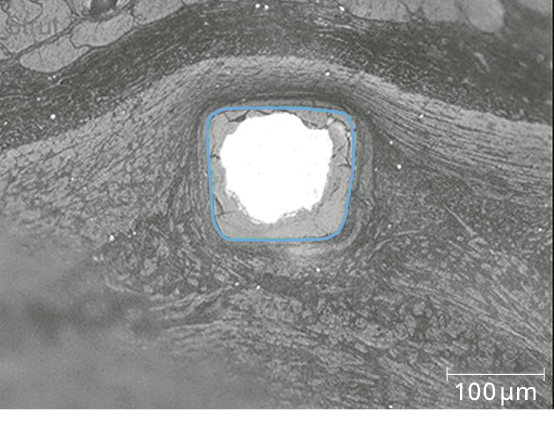

Predictable, homogeneous resorption process6

Equal resorption between struts6

Uniform shape due to homogeneous strut resorption6

Strut thickness ø 2.5 mm: 99 μm; ø 3.0/3.5 mm: 117 μm;

ø 4.0 mm: 147 μm

Drug coating BIOlute™ resorbable Poly-L-Lactide (PLLA) eluting a limus drug